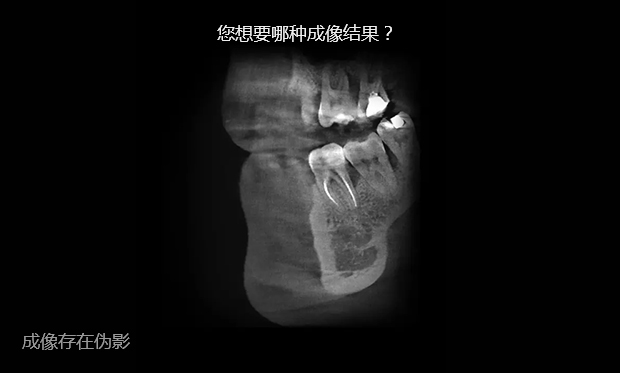

传统CT的二维扇形束扫描,投影数据是一维的,重建后的图像数据是二维的,经过重组的三维图像是连续多个二维切片堆积而成的,金属伪影较重。在数字化口腔诊疗的全链条中,数据精度决定治疗效果,对此,麦芽口腔采用三维锥形束X线取代扇形螺旋CT,二维的投影数据重建直接获取三维图像,牙齿或颌骨等硬组织结构成像质量更好。

360°扫描实时重建立体图像,突破二维X光片

限制,为您把辐射降到更低 -